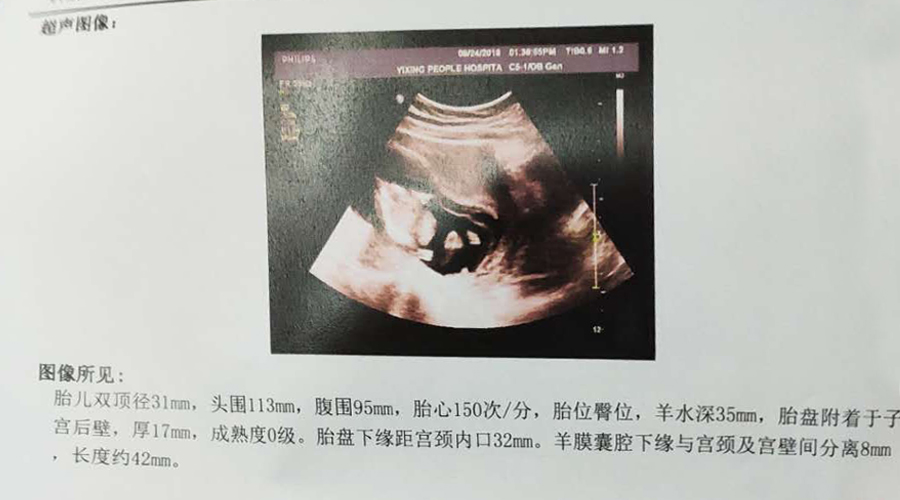

在做羊水穿刺之前去人民医院做了之前预约好的大排畸,除了那顽固的宫腔积液,其他一切正常,胎儿特别调皮,在肚子里像滚筒洗衣机一样翻来覆去,B超医生都忍不住感叹这宝宝真皮,动个不停。此刻的心情是欢愉的,甚至忘记了一周后的羊水穿刺手术。